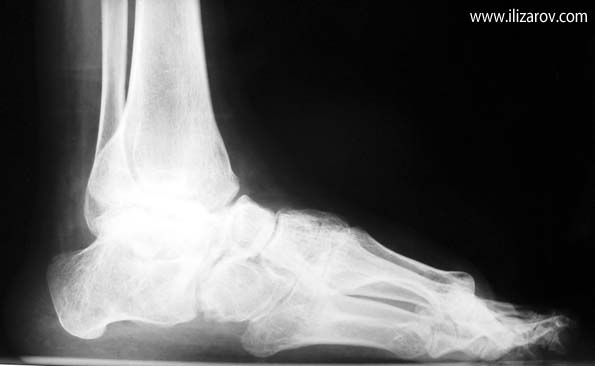

Complex foot deformities can ocur after trauma, neglected or relapsed clubfoot, poliomyelitis, osteomyelitis, burn contracture, neuromuscular diseaes and similar disorders. When treating this deformity with wide soft tissue releases, osteotomies and arthrodesis, there are disadvantages such as the risk of neurovascular injury, soft tissue problems and shortening of the foot. Besides, treating previously operated cases is even harder.

The aim of treatment in foot deformities is to acquire painless and fuctional foot which is plantigrade and at normal size. With the Ilizarov method, correction is planned in 3 planes and performed at a rate depending on the type and degree of the deformity. The deformity is corrected without shortening of the foot, with minimal surgical morbidity and the rate and direction of correction is controlled by the surgeon.

Using the Ilizarov method, foot deformities can be corrected either with or without osteotomy. The system without osteotomy corrects deformities through joints. This technique can be used in patients smaller than 8 years of age and without fixed bony deformity. For patients older than 8 years of age with fixed bony deformity and patients with neuromuscular diseases, in whom maintaining soft tissue correction is very hard, osteotomy is required.